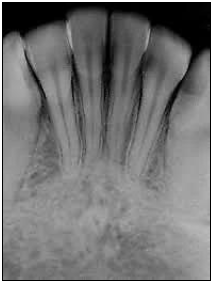

Q24716

Qual é a área radiografada mostrada na figura?